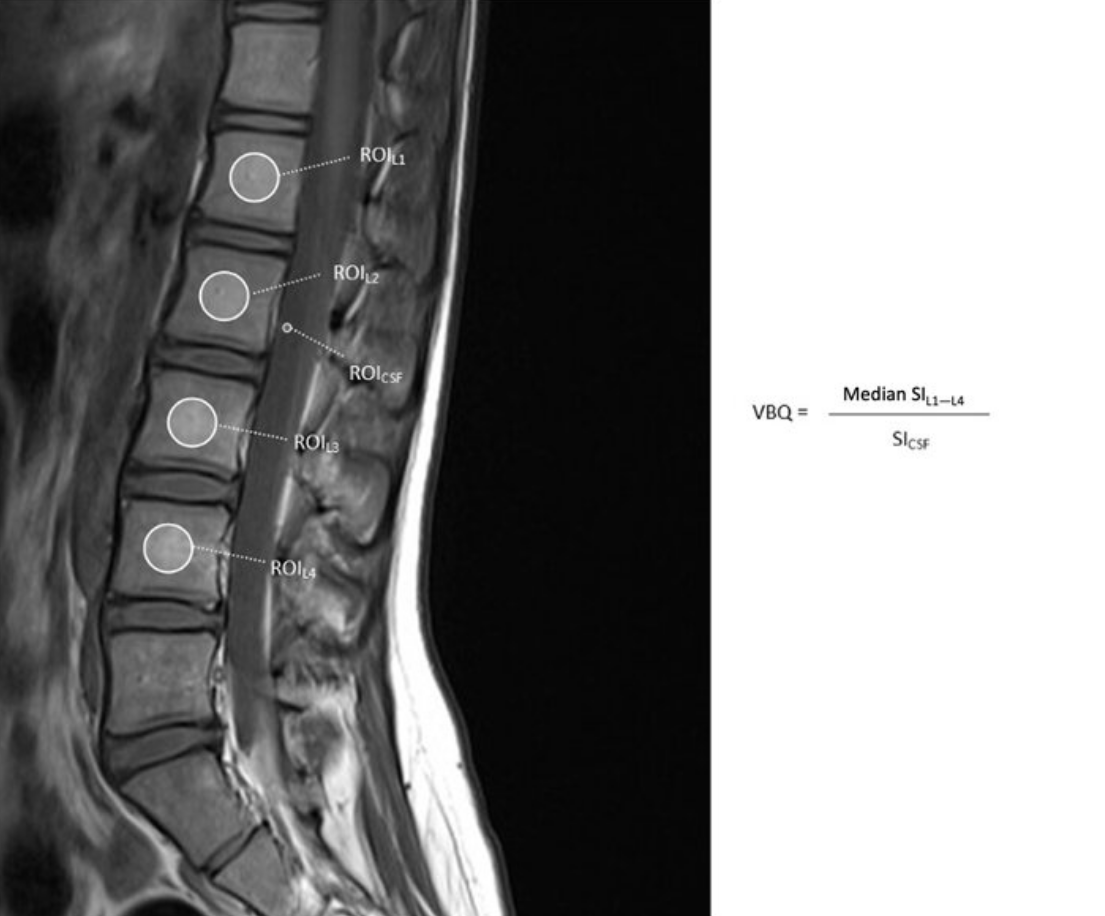

The Vertebral Bone Quality (VBQ) score is an MRI-based measure that quantifies vertebral bone marrow signal intensity to assess bone quality. It serves as an opportunistic screening tool for osteoporosis and bone quality assessment in patients undergoing spine imaging. The VBQ score reflects bone marrow composition, with higher scores indicating increased fat content in the marrow (which correlates with decreased bone quality). The score is calculated as a ratio of vertebral body signal intensity to cerebrospinal fluid (CSF) signal intensity on non-contrast T1-weighted MRI sequences.

• Obtain midsagittal T1-weighted MRI images of the lumbar spine

• Place regions of interest (ROI) within the trabecular bone of L1-L4 vertebral bodies to measure median signal intensity

• A separate region of interest is placed within the cerebrospinal fluid (CSF) at the level of the conus or cauda equina to serve as an internal reference. Measure the signal intensity of CSF, typically at the L2 or L3 level (both are comparable)

• Calculate VBQ score = (median signal intensity of L1-L4 vertebrae) / (signal intensity of CSF), producing a normalized ratio that can be compared across patients and scanners.

Adapted from: Non-contrast-enhanced T1-weighted MRI of the lumbar spine demonstrating regions of interest used to calculate the L1–L4 vertebral body quality (VBQ) score, Journal of Clinical Medicine (Accessed on 03 Jan 2026).